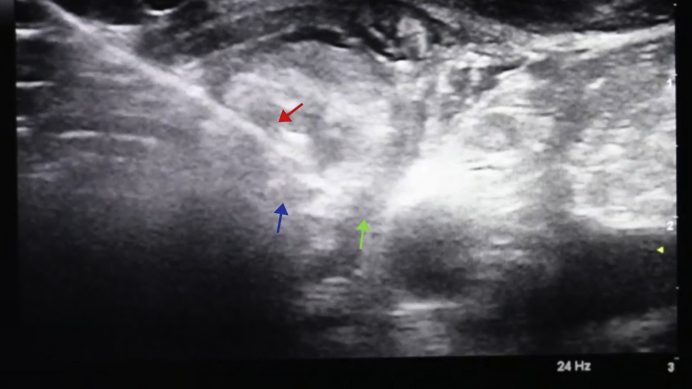

The parathyroid adenoma was again visualized in real time using ultrasound (Fig. 1); 2% lidocaine was used for local anesthesia. This was followed by hydrodissection to avoid damage to the recurrent laryngeal nerve; a total of 5 boluses of 10 mL of D5W were injected during the course of the ablation. Using the transisthmic approach, an 18-gauge RFA probe with a 0.5-cm active tip was introduced into the adenoma (Fig. 2), and ablation was started at 30 W of radiofrequency power. A total of 35 W of energy was delivered, and the total active ablation time was 1 minute. The patient tolerated the procedure well, and her vital signs remained within the normal range. Her voice remained normal, and voice strength was checked by verbalization both during and after the procedure. She was treated with enteric-coated ibuprofen for 3 days to minimize posttreatment inflammation and pain.

Fig. 2.

Ultrasound-guided RFA procedure performed with visualization of the left parathyroid adenoma in transverse view. The green arrow indicates a hypoechoic area of separation (green arrow) created between the tracheoesophageal groove/carotid artery and parathyroid adenoma by hydrodissection (ie, injection of D5W into the space between the structures). The blue arrow indicates the left inferior parathyroid adenoma. The red arrow) indicates the RFA probe with its tip within the parathyroid adenoma. The entire length of the probe was visualized as a hyperechoic line using ultrasound (transisthmic approach, parallel to the plane of the transducer). The parathyroid tissue near the needle tip became hyperechoic as it was ablated. D5W = dextrose 5% in water; RFA = radiofrequency ablation.